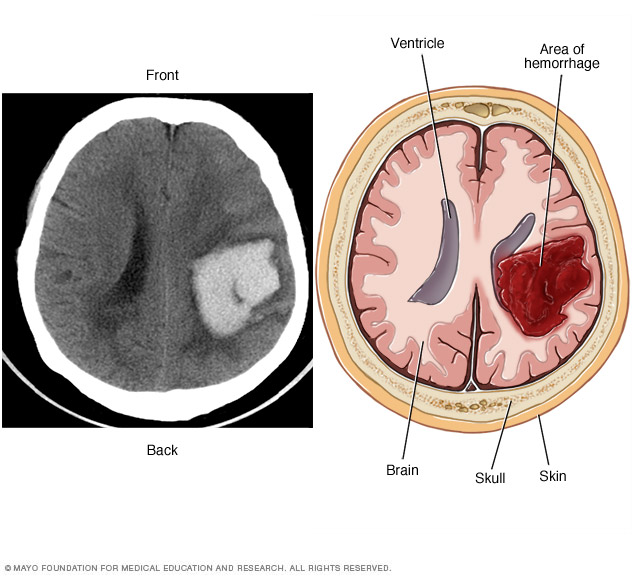

Bleeding in the brain. A brain AVM puts extreme pressure on the walls of the affected arteries and veins. The pressure causes the arteries and veins to become thin or weak. This may result in the AVM breaking open and bleeding into the brain, known as a hemorrhage.

This risk of a brain AVM bleeding ranges from around 2% to 3% each year. The risk of bleeding may be higher for certain types of AVM. Risk also may be higher in people who have had a brain AVM bleed in the past.

Some hemorrhages associated with brain AVMs aren't detected because they cause no major symptoms. However, potentially dangerous bleeding can occur.

Brain AVMs account for about 2% of all hemorrhagic strokes each year. In children and young adults who experience brain hemorrhage, brain AVMs are often the cause.